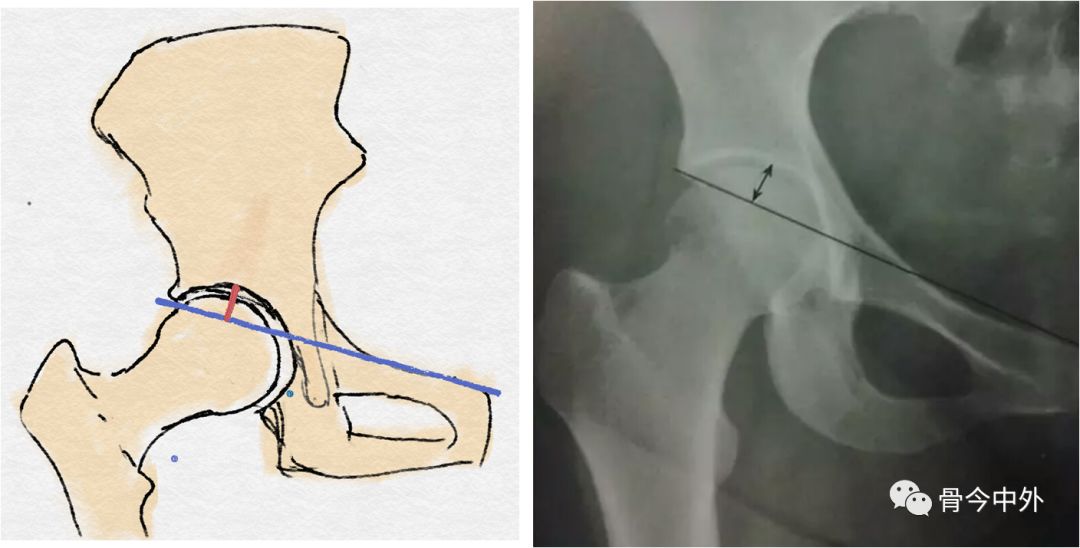

耻骨联合上缘与髋臼外上缘连线(蓝线)

蓝线至髋臼的**距离(红线)(正常:13mm)

髋臼深度:骨盆正位片,耻骨联合上缘与髋臼外上缘连线至髋臼底的**距离,正常时,男13(7~18)mm,女12(9~18)mm,与CE角配合用于评价髋臼发育情况。